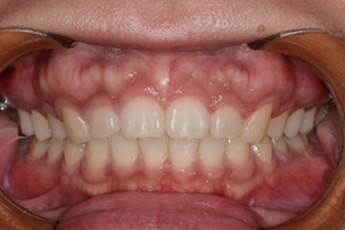

BEFORE & AFTER